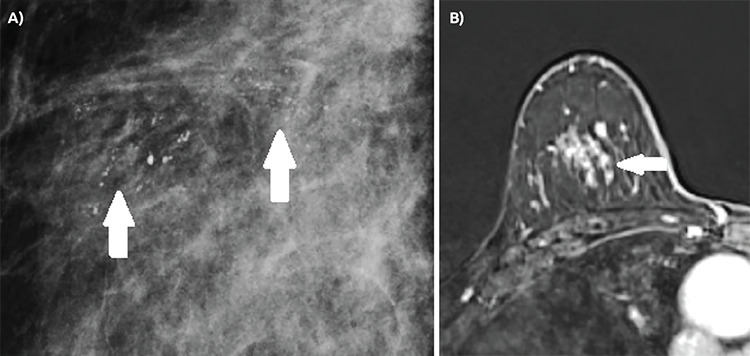

Results: Among the lesions, 44 were double HRc-positive (ER and PR-positive), 13 were single HRc-positive (ER-positive and PR-negative or ER-negative and PR-positive) and 22 were double HRc-negative (ER and PR-negative). The presence of symptom (p = 0.029), the presence of comedo necrosis (p = 0.005) and high histological grade (p<0.001) were found to be associated with ER and PR negativity. Amorphous microcalcifications were more commonly observed in the double HRc-negative group, while linear calcifications were more prevalent in both double and single HRc-positive groups (p = 0.020). Non-mass enhancement (NME) with a linear distribution was significantly more common in double HRc-negative lesions (38%), and NME with a segmental distribution in both double (43%) and single (50%) receptor-positive lesions (p = 0.042). Evaluation of DWI findings revealed that a higher lesion-to-normal breast parenchyma apparent diffusion coefficient (ADC) ratio statistically increased the probability of HRc positivity (p = 0.033).

Conclusion: Certain clinicopathological, mammography, and MRI features, along with the lesion-to-normal breast parenchyma ADC ratio, can serve as predictors for HRc status in DCIS lesions.